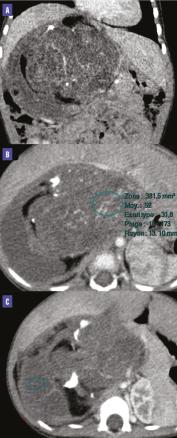

Un scanner abdomino-pelvien (figure) révèle une masse rétropéritonéale droite de 13 cm, bien limitée, à triple composante kystique, graisseuse et tissulaire, renfermant des calcifications, sans visualisation de la surrénale homolatérale. Cette masse dépend de la surrénale droite, selon les données opératoires.

Au scanner, le tératome se présente comme une tumeur à triple composante kystique, graisseuse et tissulaire. Un niveau liquide-graisse au sein de la lésion évoque un tératome mature, mais il est aussi décrit dans des liposarcomes bien différenciés.

Les calcifications sont fréquentes, caractéristiques lorsqu’elles sont présentes dans la paroi du kyste «rim sign» ou sous la forme de structures organisées (os, dents…).